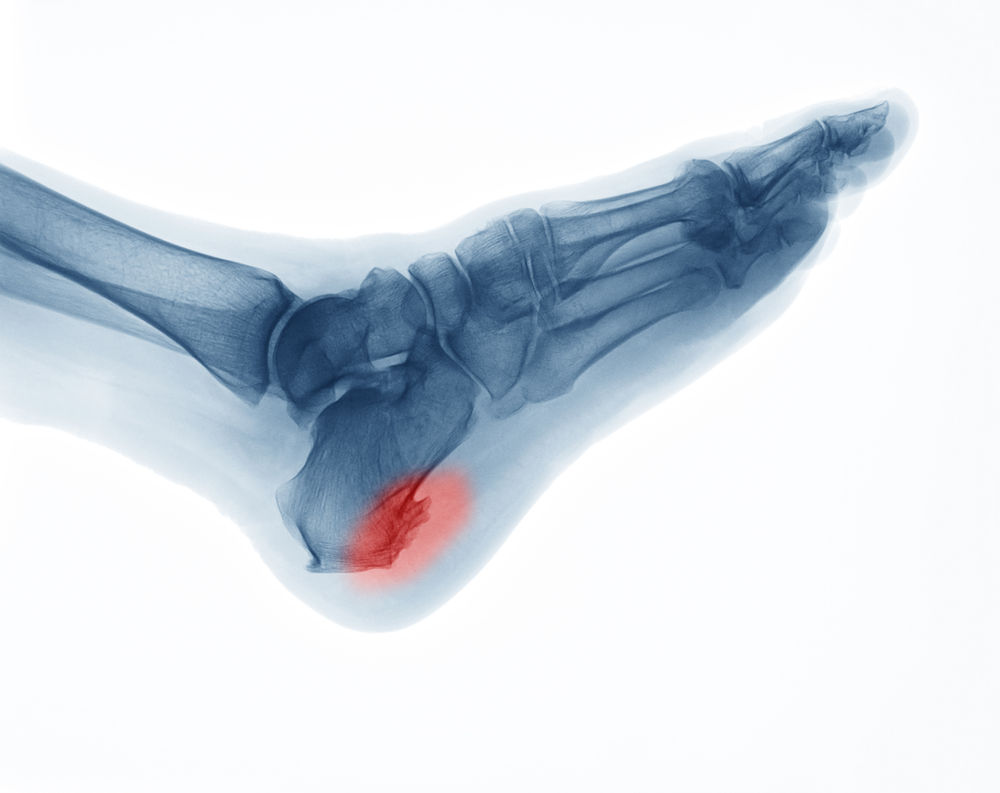

Can An X Ray Detect Plantar Fasciitis. In rare cases they might suggest an X-ray or MRI to rule out another cause like a pinched or compressed nerve or stress fracture in your heel. When seen on an X-ray a heel spur may be up to half an inch long.

Plantar fasciitis pain occurs when your plantar fascia ligaments the band of tissue that runs along the bottom of your foot tears and becomes inflamed. This area of the foot is called the plantar fascia. Plantar fasciitis pain occurs when your plantar fascia ligaments the band of tissue that runs along the bottom of your foot tears and becomes inflamed. If you feel that you are suffering from plantar fasciitis tell your doctor about it so you can be tested for it.